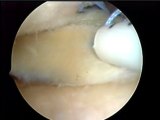

AVIVEMENT DE LA LESION

Page 35 du document :

http://www.irbms.com/rubriques/DIAPORAMAS/irbms-2009-letartre-quid-des-lesions-meniscales-abstention-regularisation-reparation.pdf